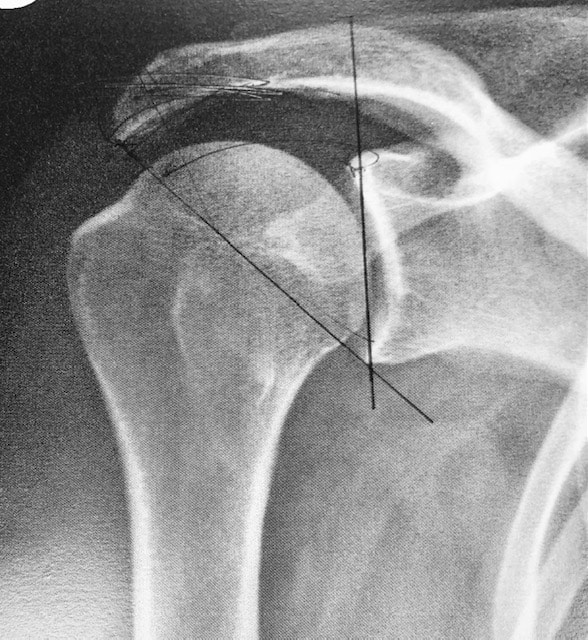

Luxation antérieure

Vue articulaire

Le traitement préconisé en cas de luxation, subluxation et instabilité, est la rééducation. Elle permet d’améliorer la stabilité et de supprimer la douleur. Si malgré la rééducation les luxations deviennent récidivantes, les subluxations trop gênantes et l’épaule instable, trop douloureuse ou invalidante, limitant les activités et gênant la qualité de vie, un bilan s’impose et une chirurgie peut être proposée. Un bilan radiographique complété d’un scanner, ou d’une IRM, et couplé à une injection de produit de contraste permet d’identifier les lésions de l’os (glène ou tête humérale) et de mettre en évidence une fissure du bourrelet, ou un arrachement des ligaments.Un bilan radiographique complété d’un scanner ou d’une IRM et couplé à une injection de produit de contraste permet d’identifier les lésions de l’os (glène ou tête humérale) et de mettre en évidence une fissure du bourrelet, ou un arrachement des ligaments.